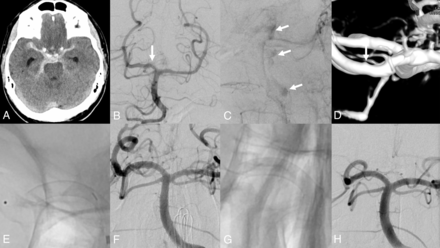

A, Initial NCCT showing the SAH. B, Axial MIP of the MRA. The suspected intracranial aneurysm of the anterior communicating artery (AcomA) and the posterior communicating artery (PcomA)/P1 can be seen (white arrows). C, DSA from the treatment. Left vertebral artery injection; a detailed view of the basilar artery head is shown. The blood-blister-like aneurysm of the P1 segment of the left posterior cerebral artery with the PcomA is demonstrated (white arrow), corresponding to the MRA, though smaller-appearing. D, Microcatheter injection. The tip of the microcatheter is in the distal left ICA, coming from the posterior via the PcomA. The left carotid-bifurcation is demonstrated (arrow). E, DSA after flow-diverter placement, reaching from the beginning of the P1 segment of the left posterior cerebral artery to the left PcomA, covering the left P1/PcomA angle (arrows pointing to the ends of the flow diverter). The aneurysm is no longer seen. F, Right ICA injection. The blood-blister-like aneurysm on the AcomA is identified, corresponding to the MRA. G, Unsubtracted view right after the deployment of the flow diverter from the A2 segment of the left anterior cerebral artery into the A1 segment of the right anterior cerebral artery. The delivering wire and the microcatheter are still in place. H, DSA after flow-diverter detachment. The aneurysm is covered but still filling with contrast (arrows indicate the ends of the flow diverter). I, Control angiogram left vertebral artery injection. The P1/PcomA aneurysm is occluded; the flow diverter is patent. J, Control angiogram of the right common carotid artery injection. The AcomA aneurysm is closed. The flow diverter is patent but shows a proximal shortening into the left A2 segment, just covering the site of the aneurysm (this is patient 1, Online Supplemental Data).